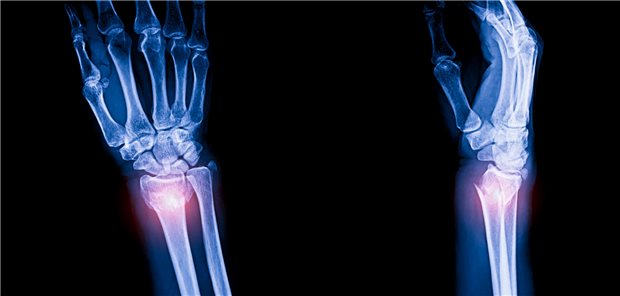

Randomisierte Studie

Distale Radiusfraktur bei Älteren: Sind operatives und konservatives Vorgehen ebenbürtig?